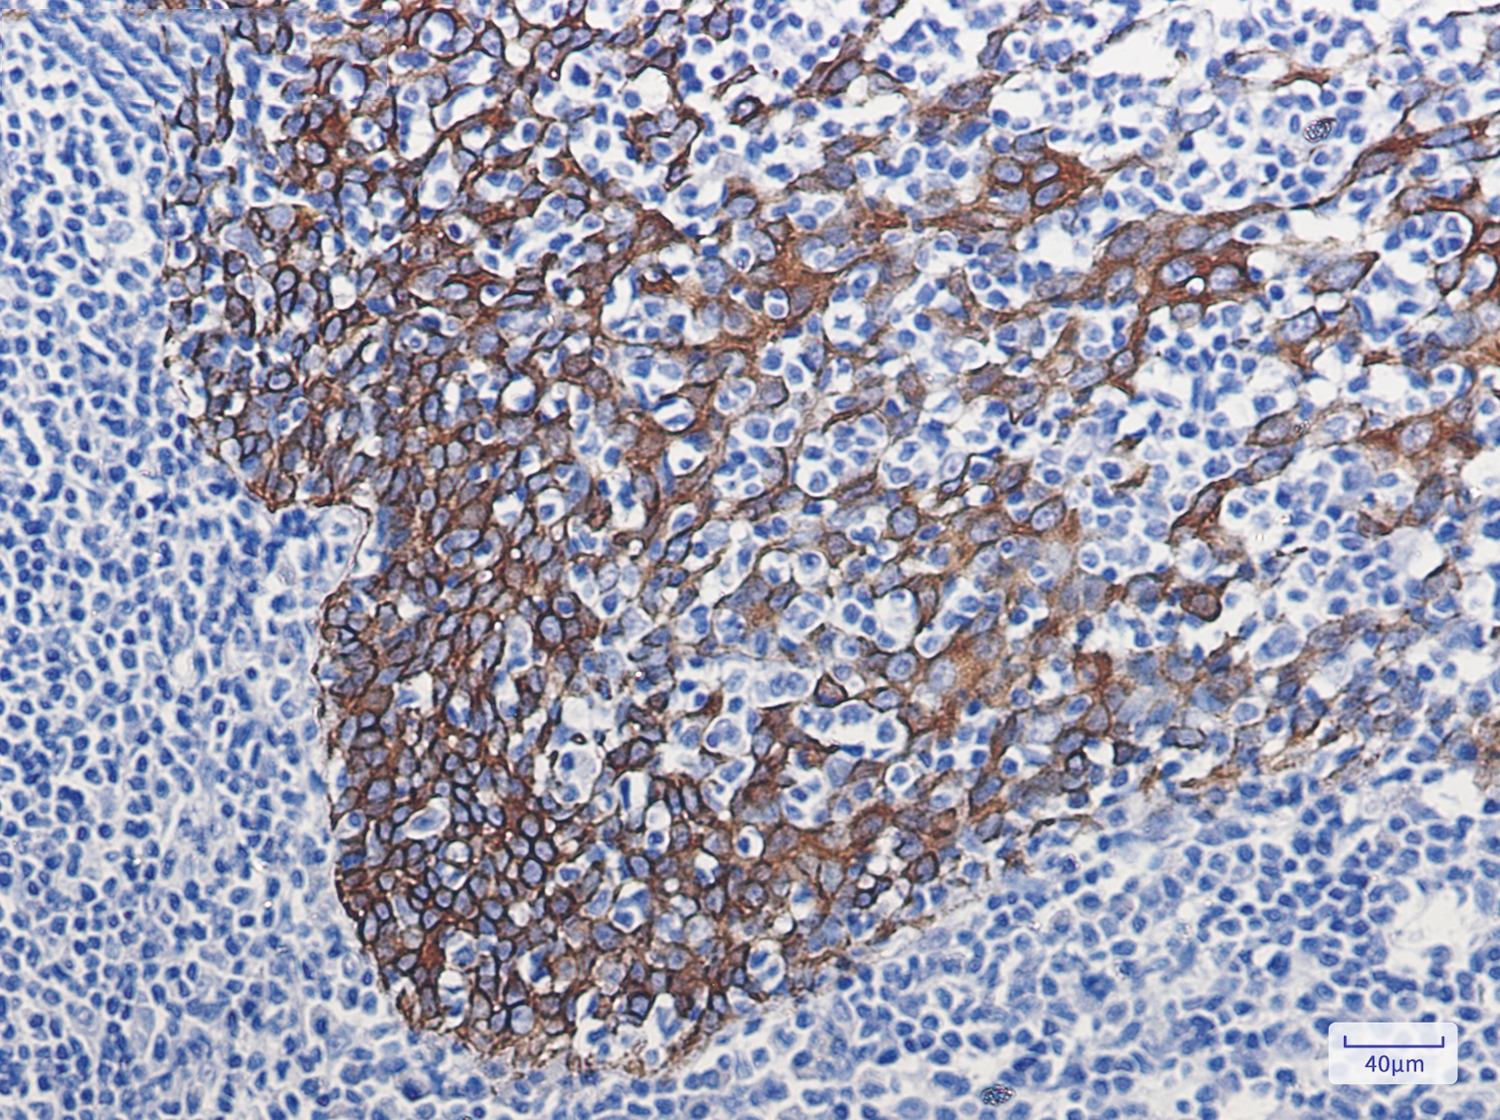

Immunohistochemistry of Cytokeratin 16 in paraffin-embedded Human tonsil using Cytokeratin 16 Rabbit mAb at dilution 1/100